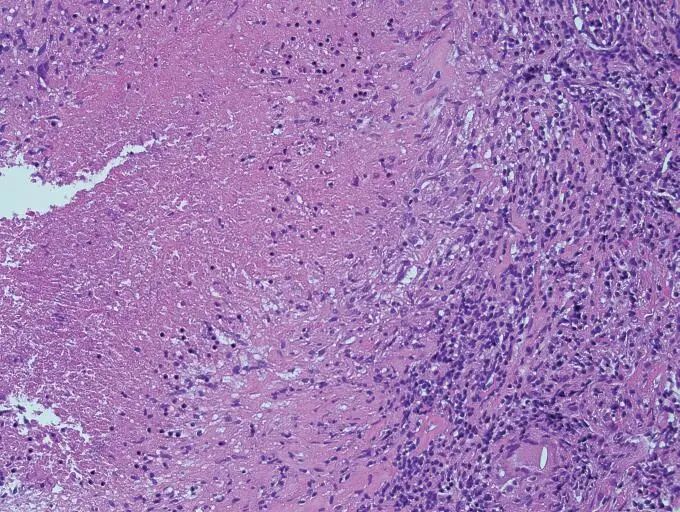

结核的典型病理

上皮样肉芽肿、干酪样坏死、朗格罕多核巨细胞。(空洞内的酪样物质里含结核菌,结核菌在液态的酪质中活跃繁殖)

详细来说,肉芽肿:巨噬细胞团,中央的巨噬细胞吞噬了细菌;上皮样组织细胞:在显微镜下,这些组织细胞看起来很像上皮细胞;多核巨细胞(Langhans巨细胞):由多个巨噬细胞融合而成,胞浆丰富,粉红色;细胞核呈马蹄样排列;干酪样坏死:肉芽肿中央可坏死,无定型状,富含脂质,来自坏死的巨噬细胞胞浆。上皮样细胞围绕在坏死物周围,呈「围栏状」(坏死过程由TNF诱导)。